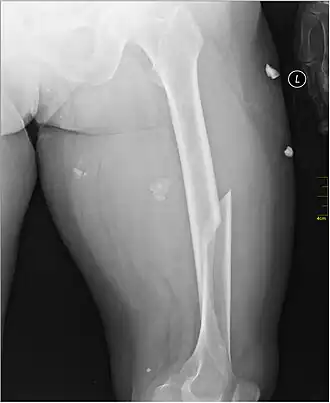

X-ray image of a femoral shaft fracture | |

A femoral fracture is a bone fracture that involves the femur. They are typically sustained in high-impact trauma, such as car crashes, due to the large amount of force needed to break the bone. Fractures of the diaphysis, or middle of the femur, are managed differently from those at the head, neck, and trochanter; those are conventionally called hip fractures (because they involve the hip joint region). Thus, mentions of femoral fracture in medicine usually refer implicitly to femoral fractures at the shaft or distally.